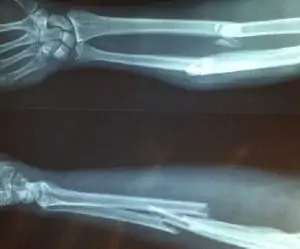

Cuando se sospecha de una fractura de cúbito y radio, el especialista llevará a cabo un examen físico detallado del antebrazo.

Se necesitarán pruebas de diagnóstico adicionales, como radiografías y resonancias magnéticas, para evaluar la lesión con mayor precisión.